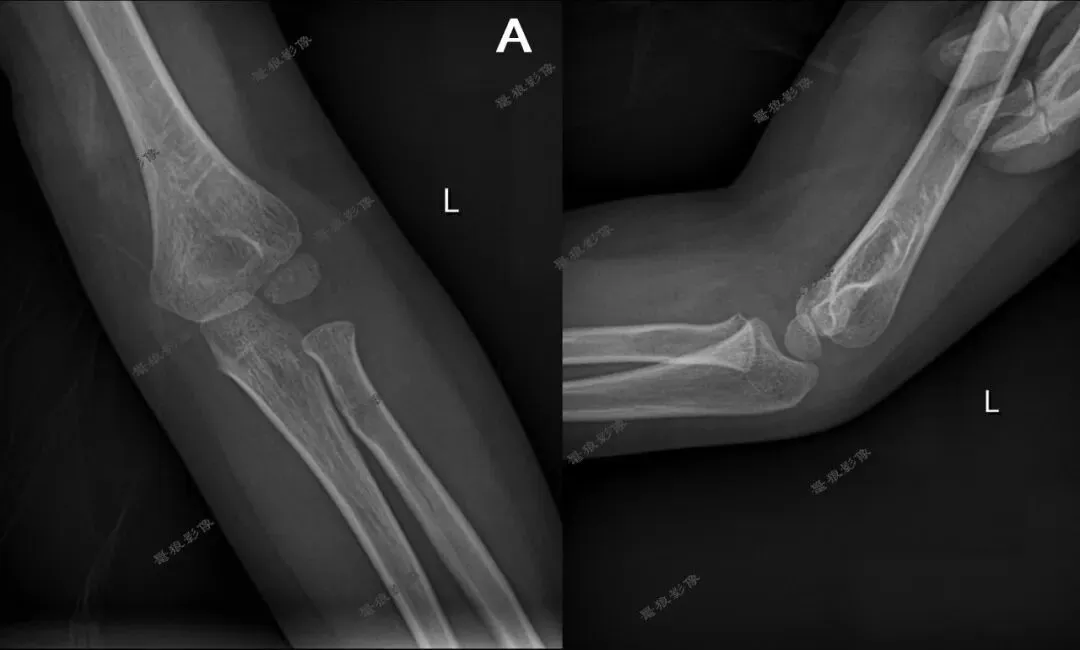

一、先来看几组图片

二、肘关节前后位

2.肘关节正位片标准影像显示:

(1)图像包括肱骨远端及桡尺骨近端,其关节间隙显示在图像正中;

(2)肘关节面呈切线位显示,明确锐利;

(3)鹰嘴窝位于肱骨内外髁正中稍偏尺侧;

(4)肘关节诸骨纹理和周围软组织清楚可见。

三、肘关节侧位

2.肘关节侧位片标准影像显示:

(1)肱骨远端与桡尺骨近端成90°~120°;

(2)尺骨与肱骨的关节间隙显示明确、锐利;

(3)肱骨内外髁重叠,呈圆形投影;

(4)肘关节诸骨纹理清晰,周围软组织层 次分明。